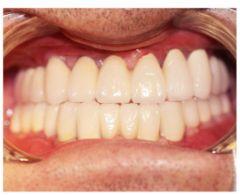

種植修復(fù)后照片